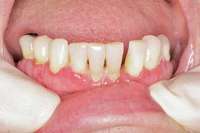

Bisphosphonate-related osteonecrosis of the jaws (BRONJ) is characterized by the presence of exposed bone in the oral cavity for more than 8 weeks in a patient who has been taking bisphosphonates and who has not had any radiation therapy in the oral cavity3 (Figure 1). The risk of BRONJ from the use of oral bisphosphonates is very low, currently about 1%.8 Most researchers believe this incidence is so low because it takes many years for the drug to saturate the bone. Most cases of BRONJ from oral bisphosphonates occur after at least 3 years of drug use.9 However, a recent study by Cartsos et al of over 700,000 medical claims found no increased incidence of inflammatory conditions, including osteonecrosis.10

Figure 1 Exposed bone in the mandibular jaw that is characteristic of BRONJ. Photo courtesy of Robert Marx, DDS.